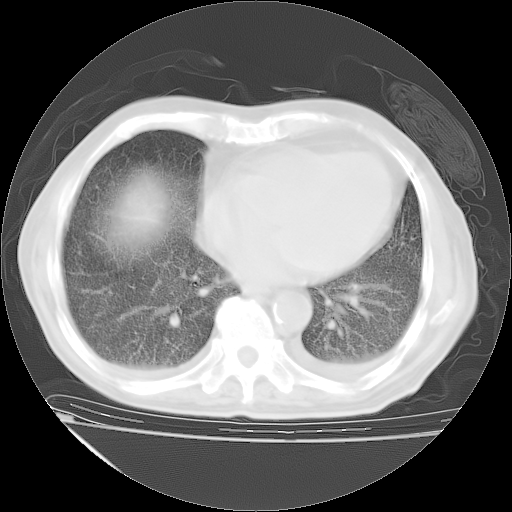

经过24天治疗,岳父的病情基本稳定。生活基本可以自理,可以下床活动。呼吸困难早已消失。体温基本正常。

只是甲强龙用80mg时血小板升到正常,改为60mg后又降到63×10*9/L。

主要治疗甲强龙80mg×14天,60mg×10天;同时抗结核(异烟肼+利福平+乙胺丁醇)。环磷酰胺0.1 tid 10天。

特别感谢胡教授、高管、桃子版主给出关键的治疗建议。桃版把所有肺部影像和全部临床资料请所在医院呼吸科、感染病科、结核科、临床免疫科专家会诊。临床免疫科专家制定了完整的治疗方案。